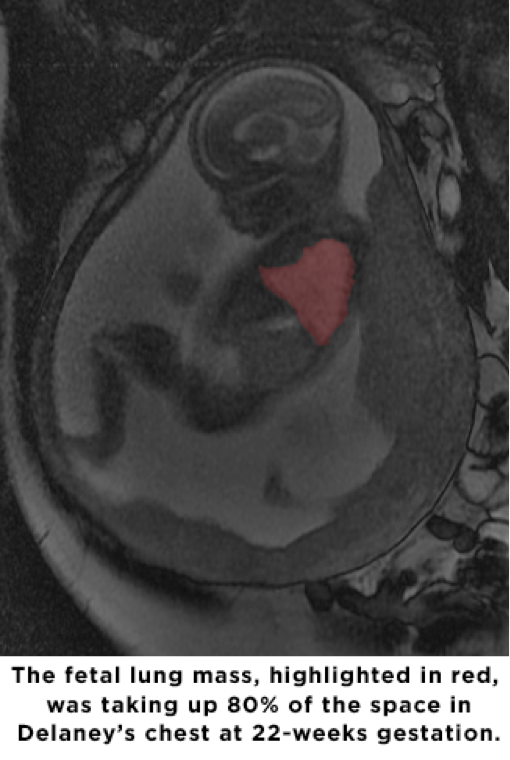

St. Louis Fetal Care Institute Develops Life Saving Before Birth Are Fetal Lungs Filled With Fluid As the fluid increases, it can. fetal pleural effusion is an accumulation of fluid in the chest cavity of a developing fetus. This liquid is produced by the fetal lung and leaves via the trachea. lung fluid is produced by epithelial cells as early as 6 weeks and plays a vital role in maintaining fetal lung expansion. . Are Fetal Lungs Filled With Fluid.